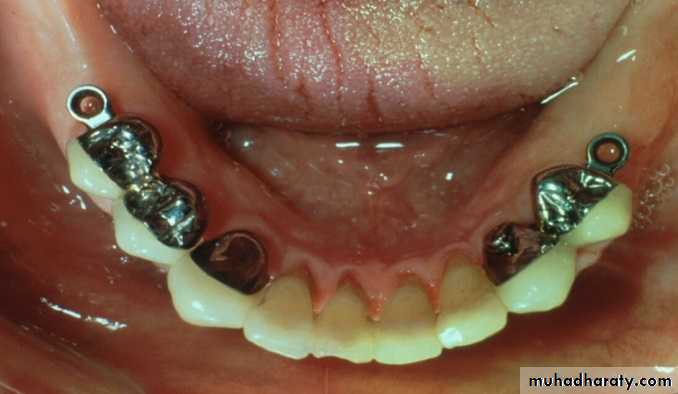

UNFAVORABLE ATTACHMENT APPLICATION:Stud Attachments

►Snap fasteners, mainly used for overdenture support, retention & stability.

► They consist of two main components:

Male projection

Female part► The two components interlock to form a retentive unit, mechanically attaching the superstructure to the abutments.

Advantages of stud attachments

►Among the simplest of all attachments► Their retentive elements can be reactivated or replaced

• ► Have applications for both root & implant supported prosthesis